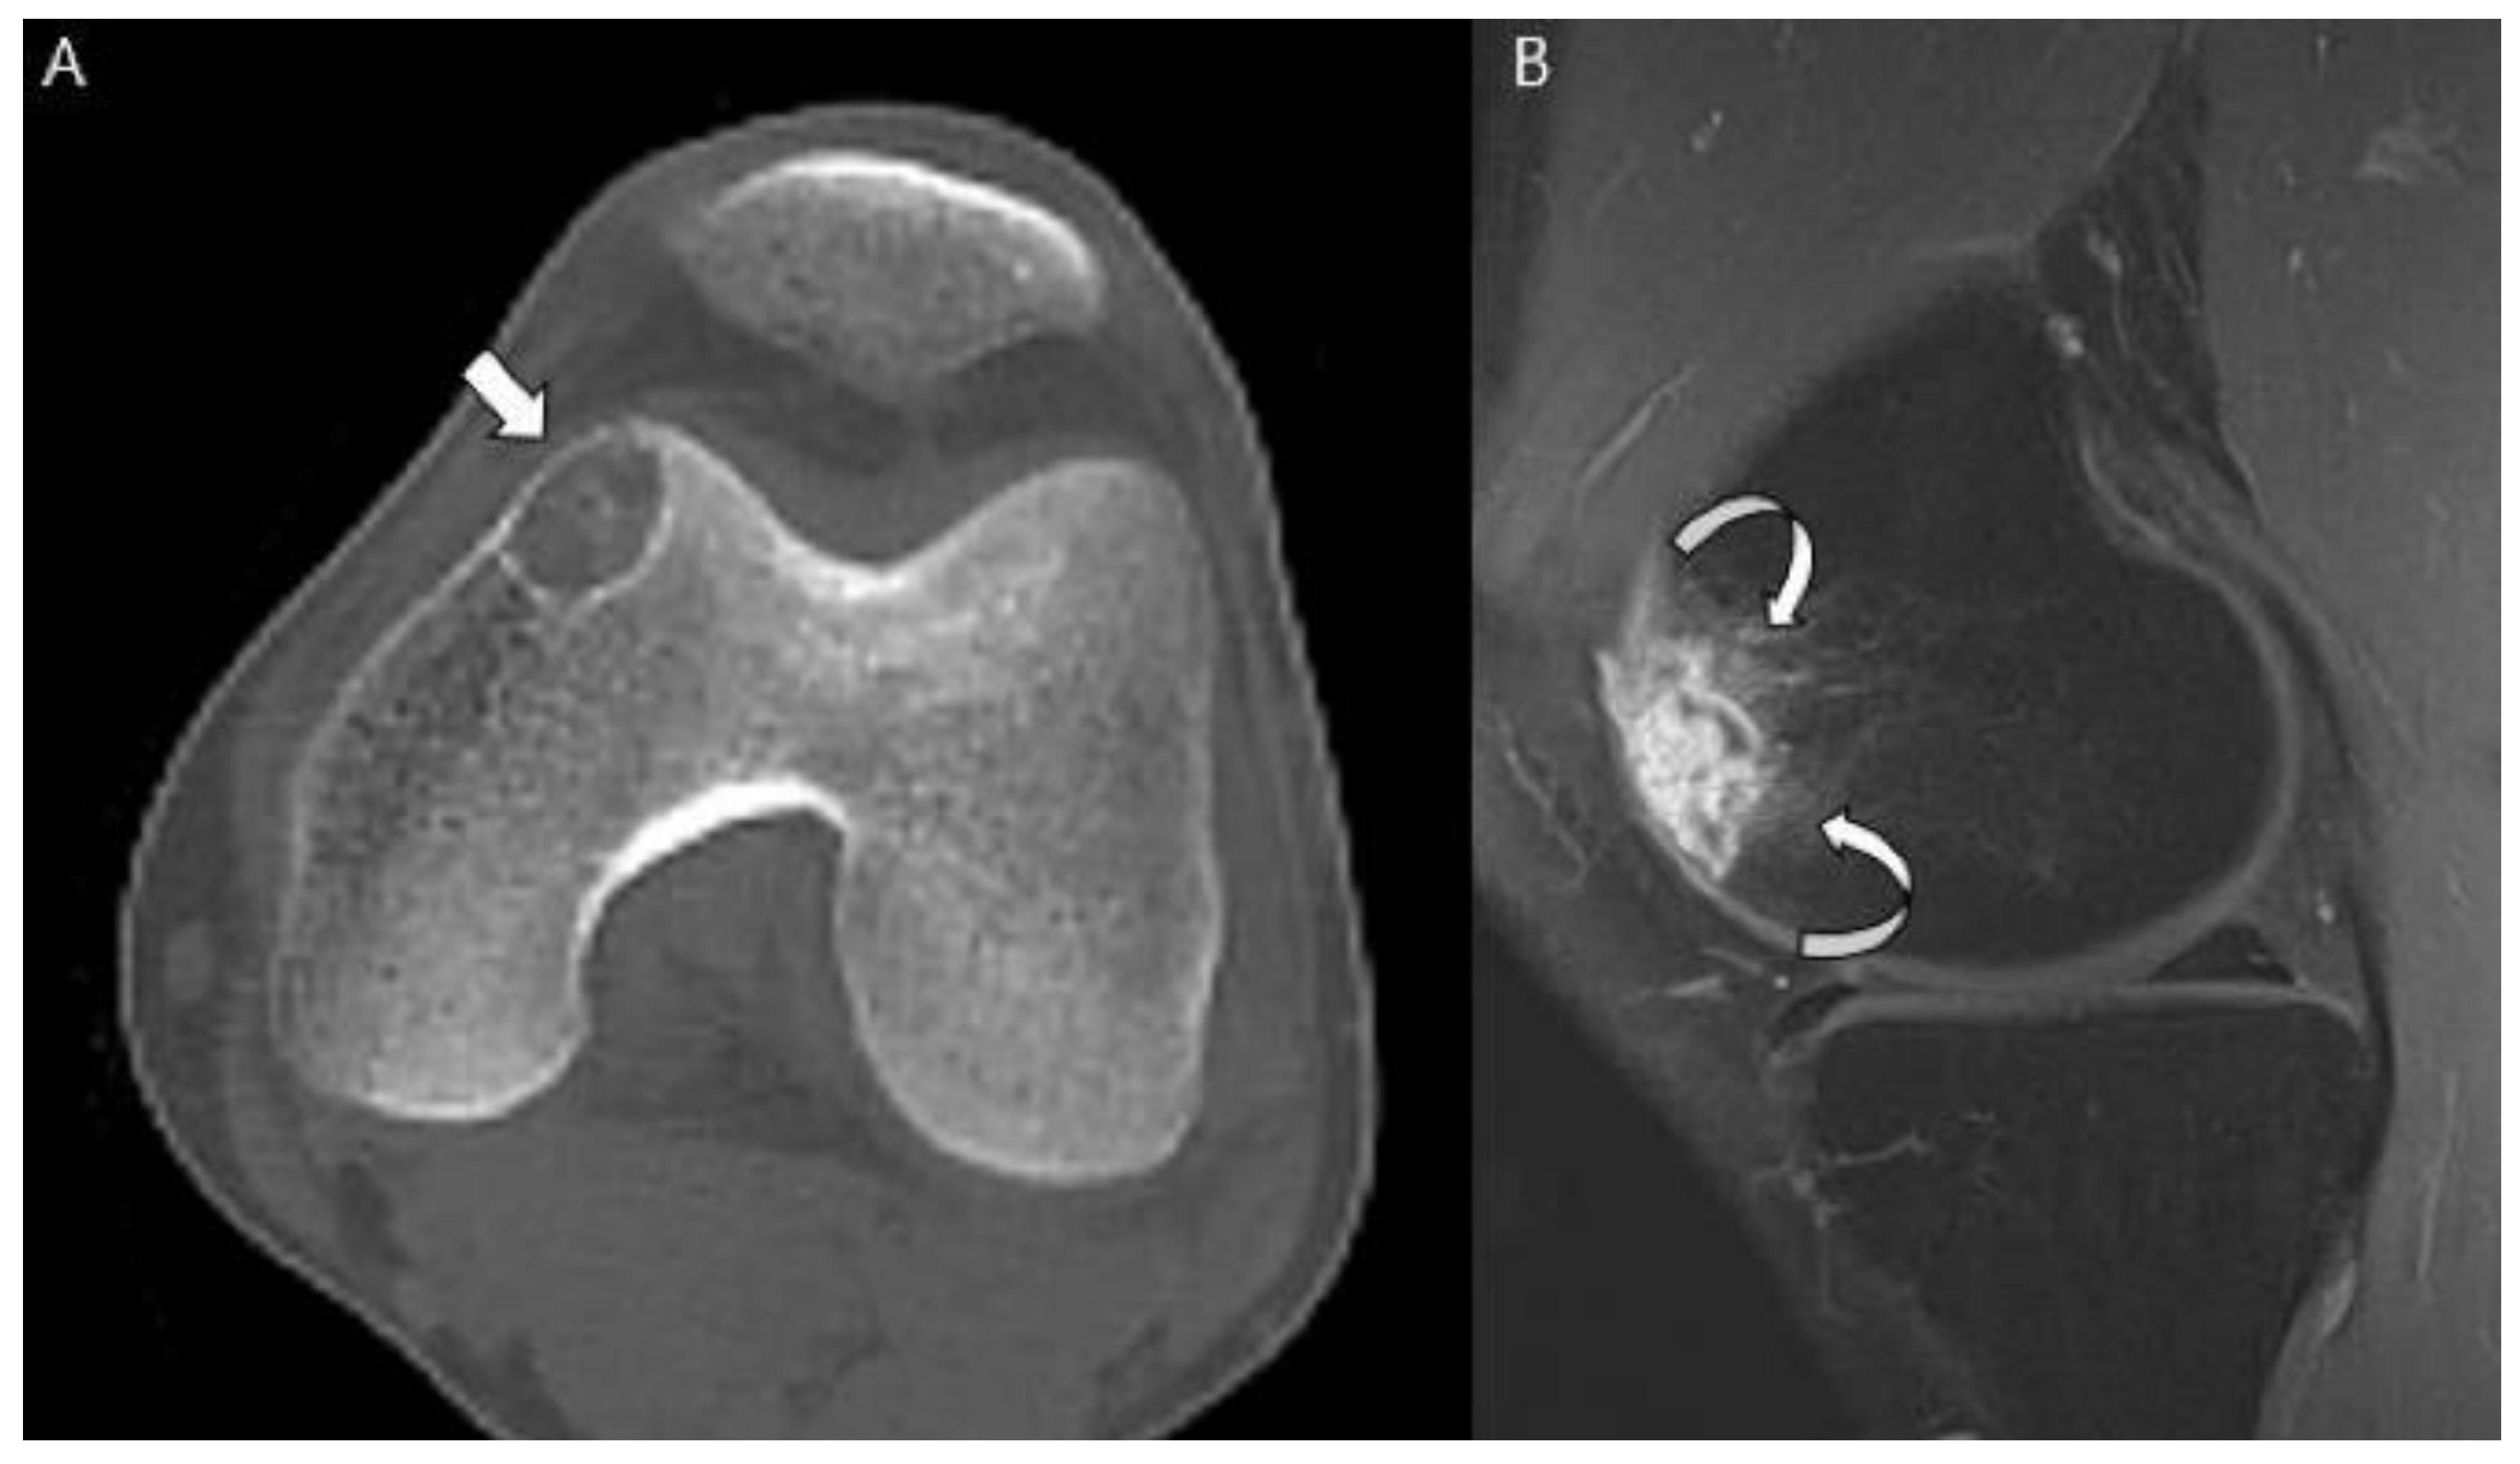

- Collins, M.S.; Koyama, T.; Swee, R.G.; Inwards, C.Y. Clear cell chondrosarcoma: Radiographic, computed tomographic, and magnetic resonance findings in 34 patients with pathologic correlation. Skelet. Radiol. 2003, 32, 687–694. [Google Scholar] [CrossRef]

- Kumar, R.; David, R.; Cierney, G., 3rd. Clear cell chondrosarcoma. Radiology 1985, 154, 45–48. [Google Scholar] [CrossRef]

- Bagley, L.; Kneeland, J.B.; Dalinka, M.K.; Bullough, P.; Brooks, J. Unusual behavior of clear cell chondrosarcoma. Skelet. Radiol. 1993, 22, 279–282. [Google Scholar] [CrossRef]

- PPresent, D.; Bacchini, P.; Pignatti, G.; Picci, P.; Bertoni, F.; Campanacci, M. Clear cell chondrosarcoma of bone. Skelet. Radiol. 1991, 20, 187–191. [Google Scholar] [CrossRef] [PubMed]